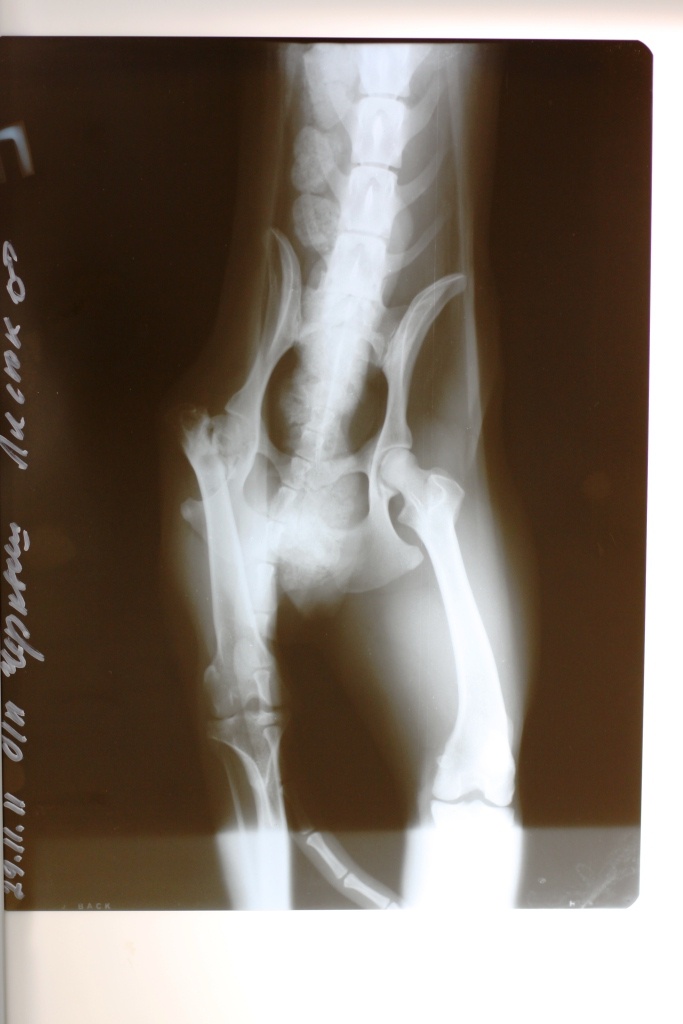

Пес средний, черный, худющий, скачет на 3-х лапах(одна усохшая, предположительно стукнутый машиной),у него скорее всего врожденно уродство-носопырка (типа заячьей губы...не могу объяснить) напуганно-ошалевший и никому не доверяющий...

еще вчера мне сказали, что когда на него в день отлова надели ошейник, он вырвался и упал с крыльца и у него !что-то с шеей" ) Фото его нету...Так вот...собираемся его ловить, да-жалко, да-невозможно закрыть глаза и пройти мимо...